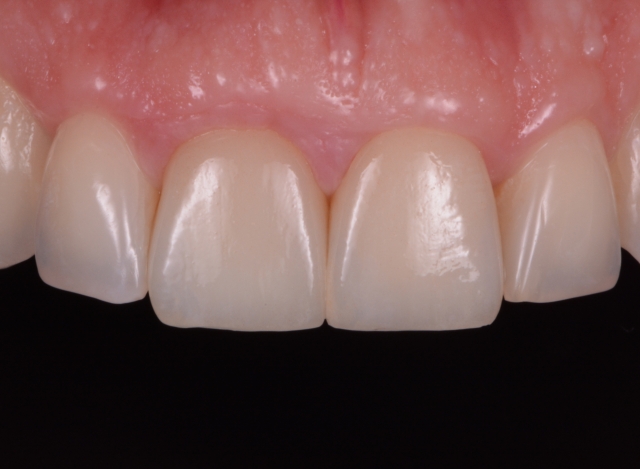

A prerequisite for long-lasting indirect restoration is a perfect marginal fit, which requires a precise impression. A perfect impression should be captured, in an un-deformed manner, of the entire configuration of the prepared tooth and some of the pristine tooth structures beyond the finishing line.

While doing so, special attention is required to prevent damage to the finishing line captured previously in the set putty. The second cord is gently removed, and at the same time, the low-viscosity PVS material is injected into the tray.

The loaded tray is placed over the prepared teeth to a full seat while the first, deeper cords remain in place. Sometimes the first cord is removed along with the impression, which should not cause problems for the technician as long as it is attached to the material and remains beyond the margins of the prepared teeth.